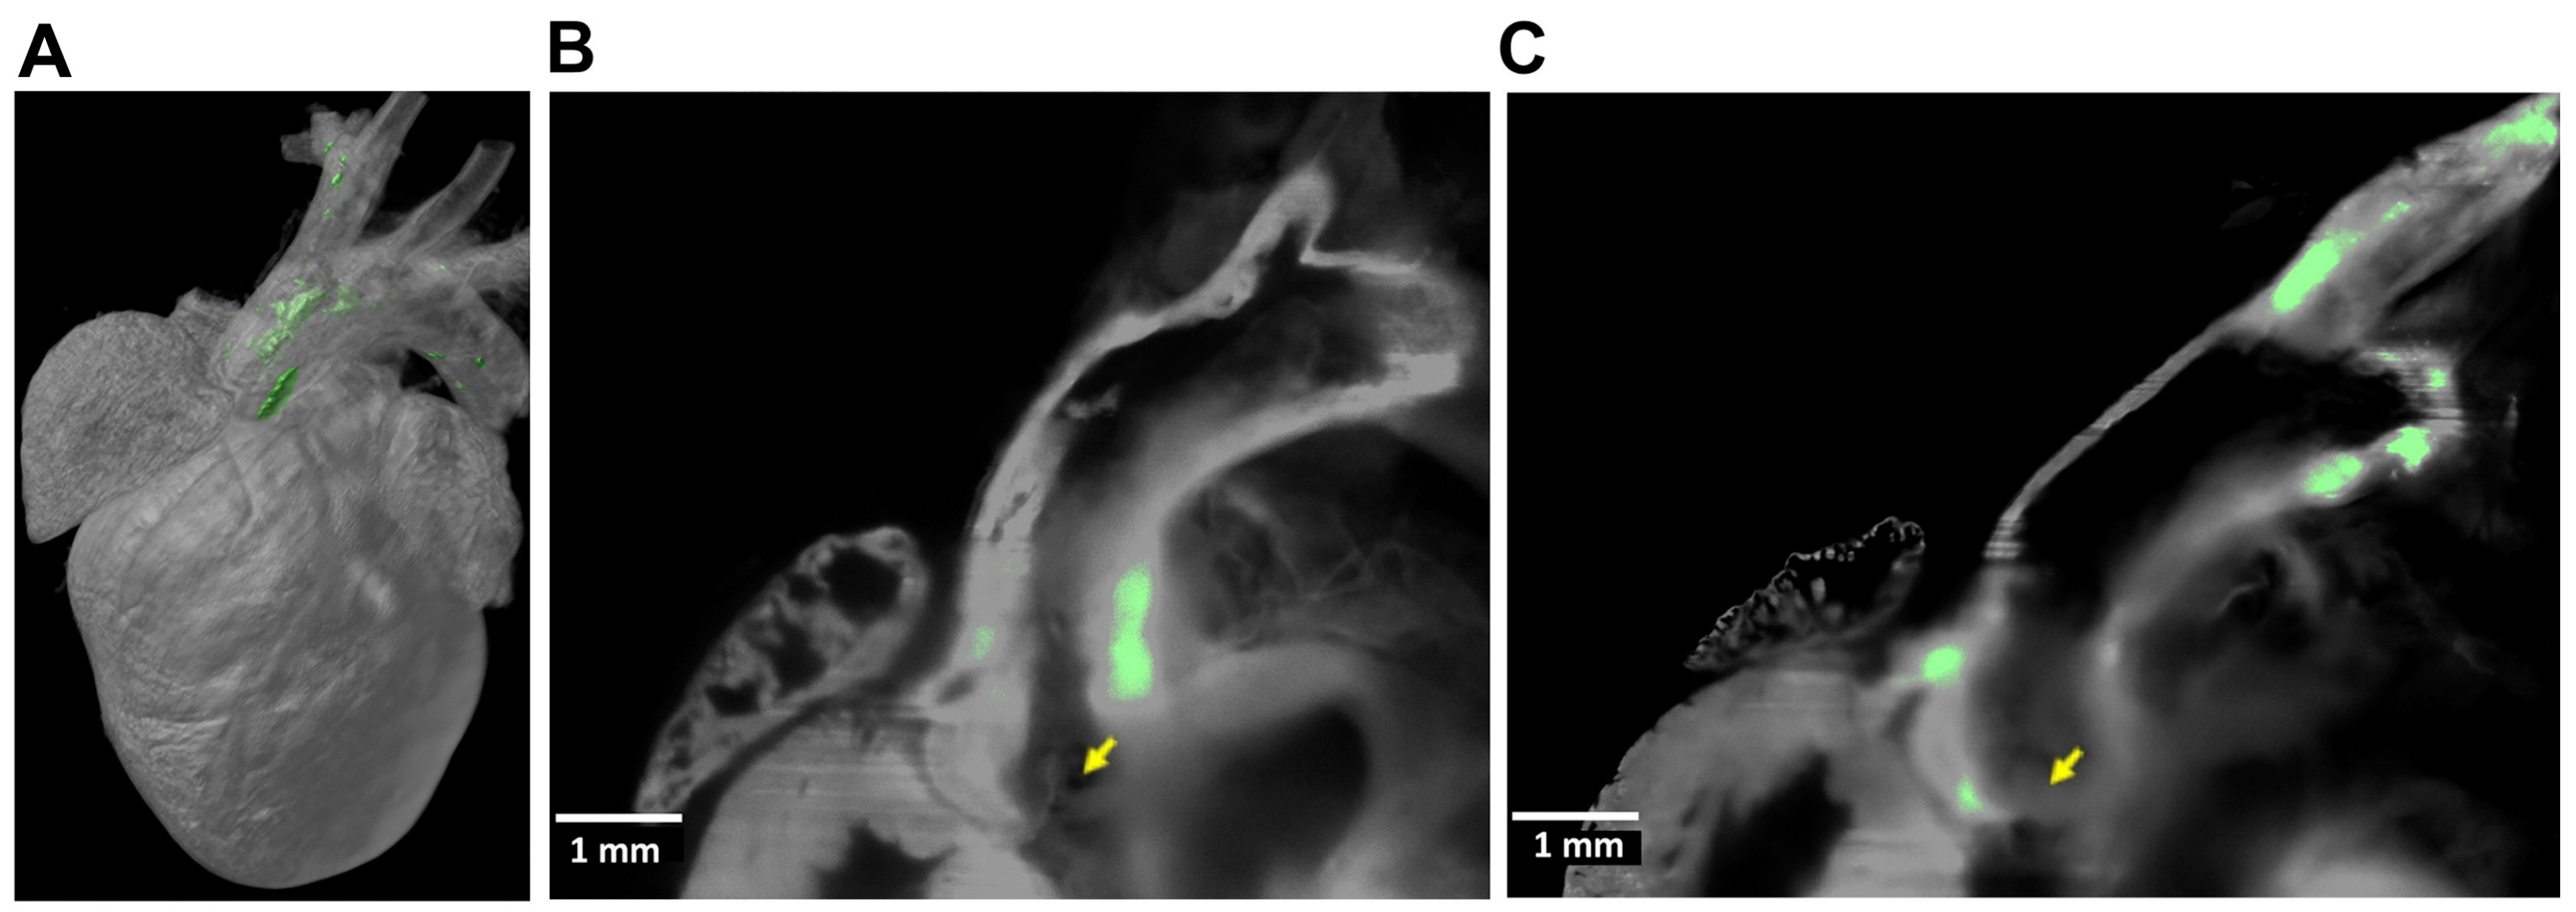

- Ding, Y.; Ma, J.; Langenbacher, A.D.; Baek, K.I.; Lee, J.; Chang, C.C.; Hsu, J.J.; Kulkarni, R.P.; Belperio, J.; Shi, W.; et al. Multiscale light-sheet for rapid imaging of cardiopulmonary system. JCI Insight 2018, 3, e121396. [Google Scholar] [CrossRef]

- Baek, K.I.; Ding, Y.; Chang, C.C.; Chang, M.; Packard, R.R.S.; Hsu, J.J.; Fei, P.; Hsiai, T.K. Advanced microscopy to elucidate cardiovascular injury and regeneration: 4D light-sheet imaging. Prog. Biophys. Mol. Biol. 2018, 138, 105–115. [Google Scholar] [CrossRef]

- Ding, Y.; Lee, J.; Hsu, J.J.; Chang, C.C.; Baek, K.I.; Ranjbarvaziri, S.; Ardehali, R.; Packard, R.; Hsiai, T.K. Light-Sheet Imaging to Elucidate Cardiovascular Injury and Repair. Curr. Cardiol. Rep. 2018, 20, 35. [Google Scholar] [CrossRef]

- Hsu, J.J.; Vedula, V.; Baek, K.I.; Chen, C.; Chen, J.; Chou, M.I.; Lam, J.; Subhedar, S.; Wang, J.; Ding, Y.; et al. Contractile and hemodynamic forces coordinate Notch1b-mediated outflow tract valve formation. JCI Insight 2019, 5, e124460. [Google Scholar] [CrossRef]

- Ding, Y.; Abiri, A.; Abiri, P.; Li, S.; Chang, C.C.; Baek, K.I.; Hsu, J.J.; Sideris, E.; Li, Y.; Lee, J.; et al. Integrating light-sheet imaging with virtual reality to recapitulate developmental cardiac mechanics. JCI Insight 2017, 2, e97180. [Google Scholar] [CrossRef]